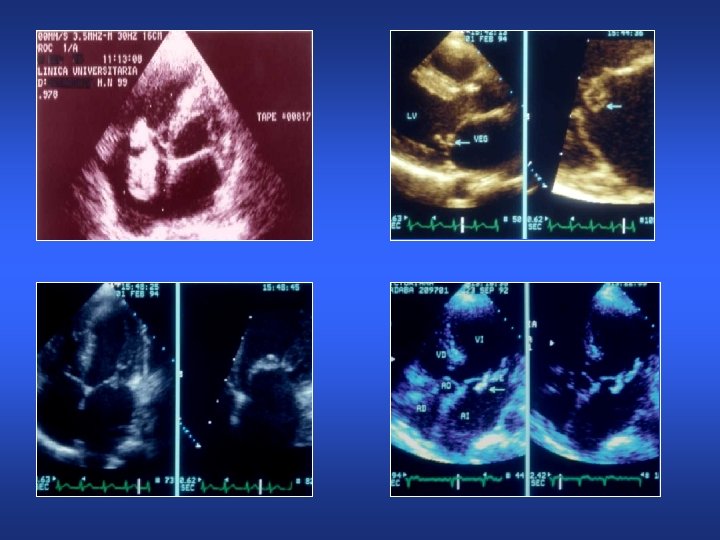

Endocarditis infecciosa Localización de vegetaciones AI Ao VI

Vegetaciones endocardíticas

Vegetaciones endocardíticas Embolismo

Endocarditis infecciosa Ecocardiograma • • • Sensibilidad (50 -90%) para vegetaciones Aumenta con ETE No detecta vegetaciones <2 mm Un estudio negativo no excluye Util para indicar Tto. Quirurgico Diagnóstico de complicaciones – – Abceso perivalvular Rotura de cuerda Fístulas Abceso miocárdico • RNM es más sensible